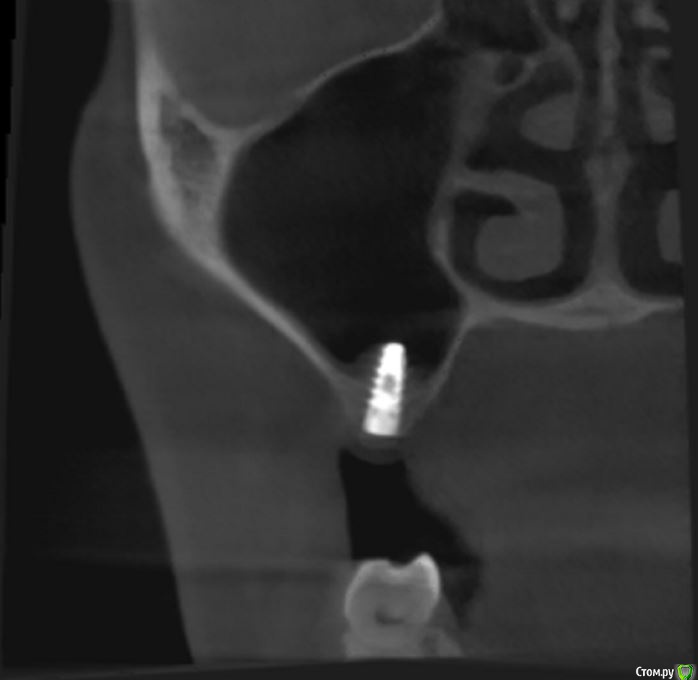

jm3300 Опубликовано 12 июля, 2016 Автор Поделиться Опубликовано 12 июля, 2016 А до операции КТ могли бы выложить? И сколько времени отсутствовали зубы в этой области?отсутствовали достаточно долги. КТ до: Ссылка на комментарий

jm3300 Опубликовано 14 июля, 2016 Автор Поделиться Опубликовано 14 июля, 2016 выкладываю кт Ссылка на комментарий

умножающий печаль Опубликовано 14 июля, 2016 Поделиться Опубликовано 14 июля, 2016 Промыть пазуху через соустье, курсом. Я отправляю к ЛОРам. Антибиотикотерапия, гипосенсибилизация. Один из винтов вестибулярно без костной поддержки, на мой взгляд. 1 Ссылка на комментарий

red_butler Опубликовано 15 июля, 2016 Поделиться Опубликовано 15 июля, 2016 гайморит всё таки есть?Не увидел, один винт похоже на выход 1 Ссылка на комментарий

syrovovec Опубликовано 15 июля, 2016 Поделиться Опубликовано 15 июля, 2016 (изменено) Пазуха чистая, Антон, какой винт на выход не понял?Может у пац аллергия ? Изменено 15 июля, 2016 пользователем syrovovec 1 Ссылка на комментарий

kladoffka Опубликовано 15 июля, 2016 Поделиться Опубликовано 15 июля, 2016 Тоже не понял, вроде все хорошо стоят. Главное слизистые то в покое. 1 Ссылка на комментарий

red_butler Опубликовано 15 июля, 2016 Поделиться Опубликовано 15 июля, 2016 Пазуха чистая, Антон, какой винт на выход не понял?Может у пац аллергия ?На последних срезах, вестибулярно на 2/3 кости нет.Какая уж аллергия, если боль и отек 1 Ссылка на комментарий

умножающий печаль Опубликовано 15 июля, 2016 Поделиться Опубликовано 15 июля, 2016 (изменено) гайморит всё таки есть?Судя по симптоматике, которую вы представили, есть. На снимке признаки могут запаздывать, ежели процесс острый, хотя снижение пневматизации должно быть заметно. Я на мониторе не разглядел. Рентген всего лишь доп. метод обследования. Диагноз ставит врач, то есть вы, сопоставив клинику и доп.методы.З.Ы. Я не думаю, что в вашем случае причина гайморита имплантация. Временной интервал слишком велик. Изменено 15 июля, 2016 пользователем умножающий печаль 1 Ссылка на комментарий

умножающий печаль Опубликовано 15 июля, 2016 Поделиться Опубликовано 15 июля, 2016 Тоже не понял, вроде все хорошо стоят. Главное слизистые то в покое.Это пока в покое. Винт не покрытый костью, долго под мягкими тканями оставаться не будет. Неизбежна рецессия со всеми вытекающими. 1 Ссылка на комментарий